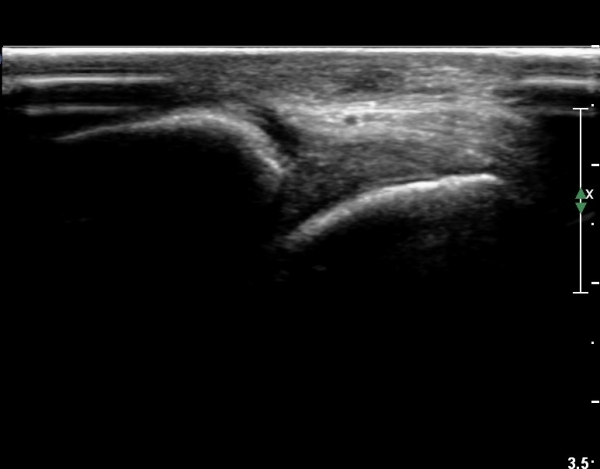

Àü¹æ ¸»´Ü °æ°ñºñ°ñÀδë Á¾´Ü¸é°Ë»ç¿¡¼­ ºñ°ñ ºÎÀ§ °æ°ñºñ°ñÀδëÀÇ Àú¿¡ÄÚºÎÁ¾ÀÌ °üÂûµÇ°í

ºÎÇϰ˻翡¼­ ºñ°ñÀÇ °úµµÇÑ ¿òÁ÷ÀÓÀÌ °üÂûµÈ´Ù(»çÁø 1, 2, µ¿¿µ»ó 1).